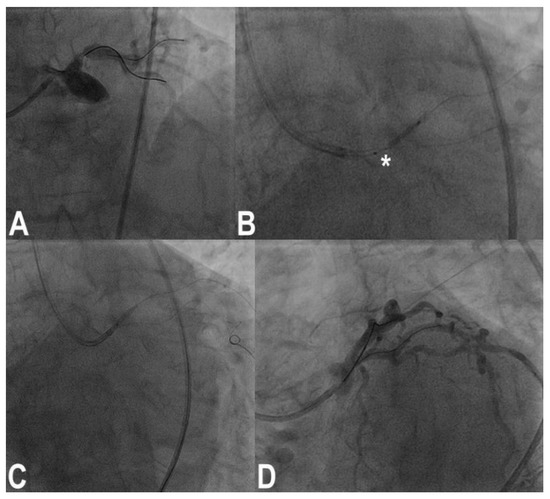

3.9. Balloon Entrapment